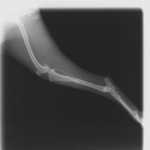

症例:交通事故による椎体脱臼

柴犬:9歳、避妊雌

交通事故直後、胸腰部に激しい疼痛、両後肢に完全麻痺を認め、シェフシェリントン徴候を呈していました。レントゲン検査において、第11-12胸椎間の脱臼が認められました。

脊髄の減圧、脊柱管の再構築・安定化を目的に、片側椎弓切除術およびMatrixMANDIBLE Plateによる椎体固定を実施しました。

隣接椎体を架橋するようにプレートを設置しました。

術後レントゲン写真